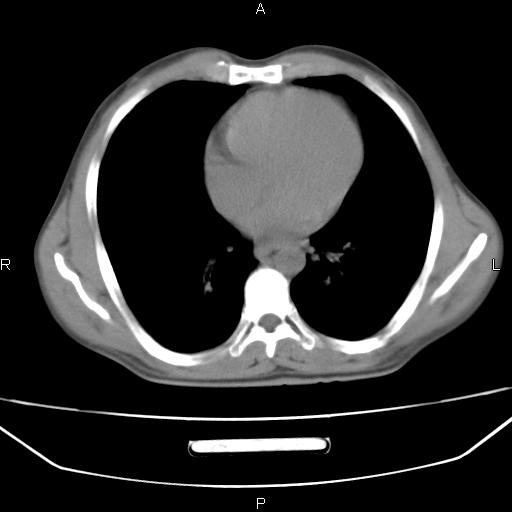

患者,男,40岁。间断发热,咳嗽二十余日。体温最高达38.9° 在当地诊所抗炎治疗三天后体温降至正常,患者自行停药。今又发热。胸片示,左下肺阴影。

左下肺片状高密度影,境界模糊,密度不均,考虑感染性病变可能性大,建议抗炎治疗后复查。左肺门增大,不除外占位性病变,必要时支气管镜检。